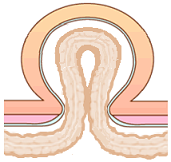

�{���Ȃ炨���̒��ɂ���͂��̕����⒰�̈ꕔ���A�l�a���i�l�a�Ƃ͉��������瑫�̕t���������̂��Ɓj�̕��ǂ̎ア�����畠���̈ꕔ���X�i�ӂ���j�ƂȂ��ēˏo���A�畆�̉��ɏo�Ă���a�C�ł��B��ʓI�ɂ͒E���i�������傤�j�ƌĂ�܂��B ���c�����獂��҂܂ŕ��L���N���肤��a�C�ł��B���c���̏ꍇ�͐�V�I�ȗv�����قƂ�ǂł����A���l�̏ꍇ�͉^���s�����܂ߐg�̂̑g�D���キ�Ȃ邱�Ƃ��v���ł��B ����40�Έȏ�̒����N�j���ɑ����݂��܂��B |

��ڃw���j�A�́A�l�a�w���j�A�����������ɋ߂��Ƃ��낪�c�i�ӂ��j��ރw���j�A�ł��B

�����Ƃ��ẮA�l�a�w���j�A�Ɠ����悤�ɁA����Ȃǂɂ��ؓ���ؖ����キ�Ȃ邱�Ƃ�A�d�����������ȂǕ�����������₷����Ԃ��������Ƃ��ɋN����₷���ƌ����Ă��܂��B